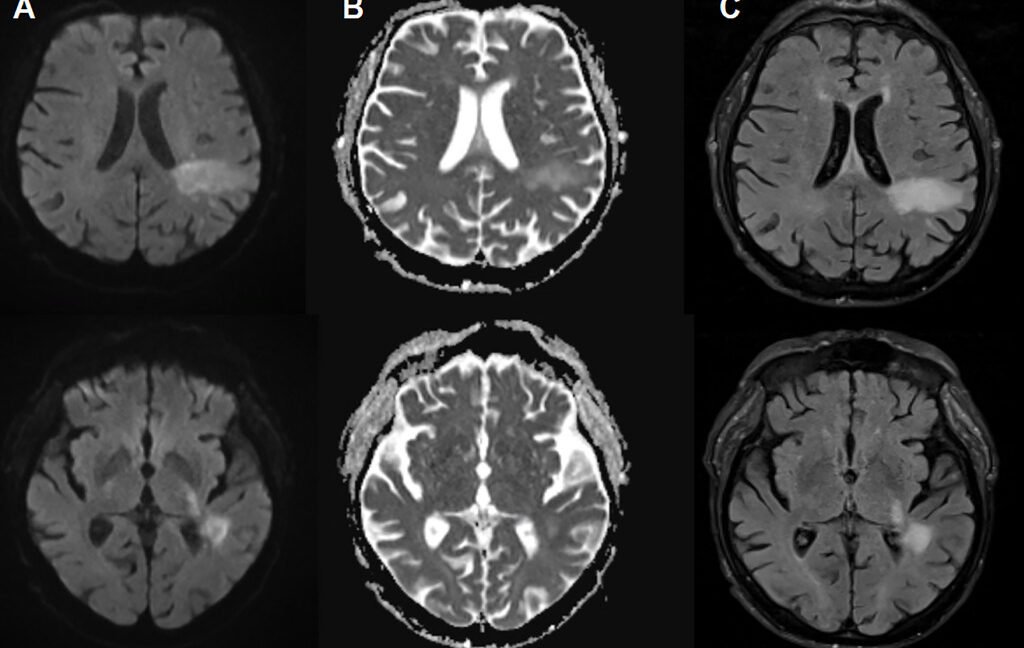

In PML, the new disease-causing virus or “PML-type” JC virus actively attacks the brain, destroying specific brain cells, including the cells that form the insulating myelin sheath that protects nerve cells. This causes widespread demyelination, resulting in nerve cell dysfunction and death. On imaging, PML may appear as signature lesions in the brain. PML is diagnosed by those imaged lesions paired with test findings of JC virus DNA in cerebrospinal fluid. But for patients experiencing PML, symptoms can mimic everything from stroke to multiple sclerosis, leading to problems like speech impairment, visual defects, motor dysfunction, and seizures.